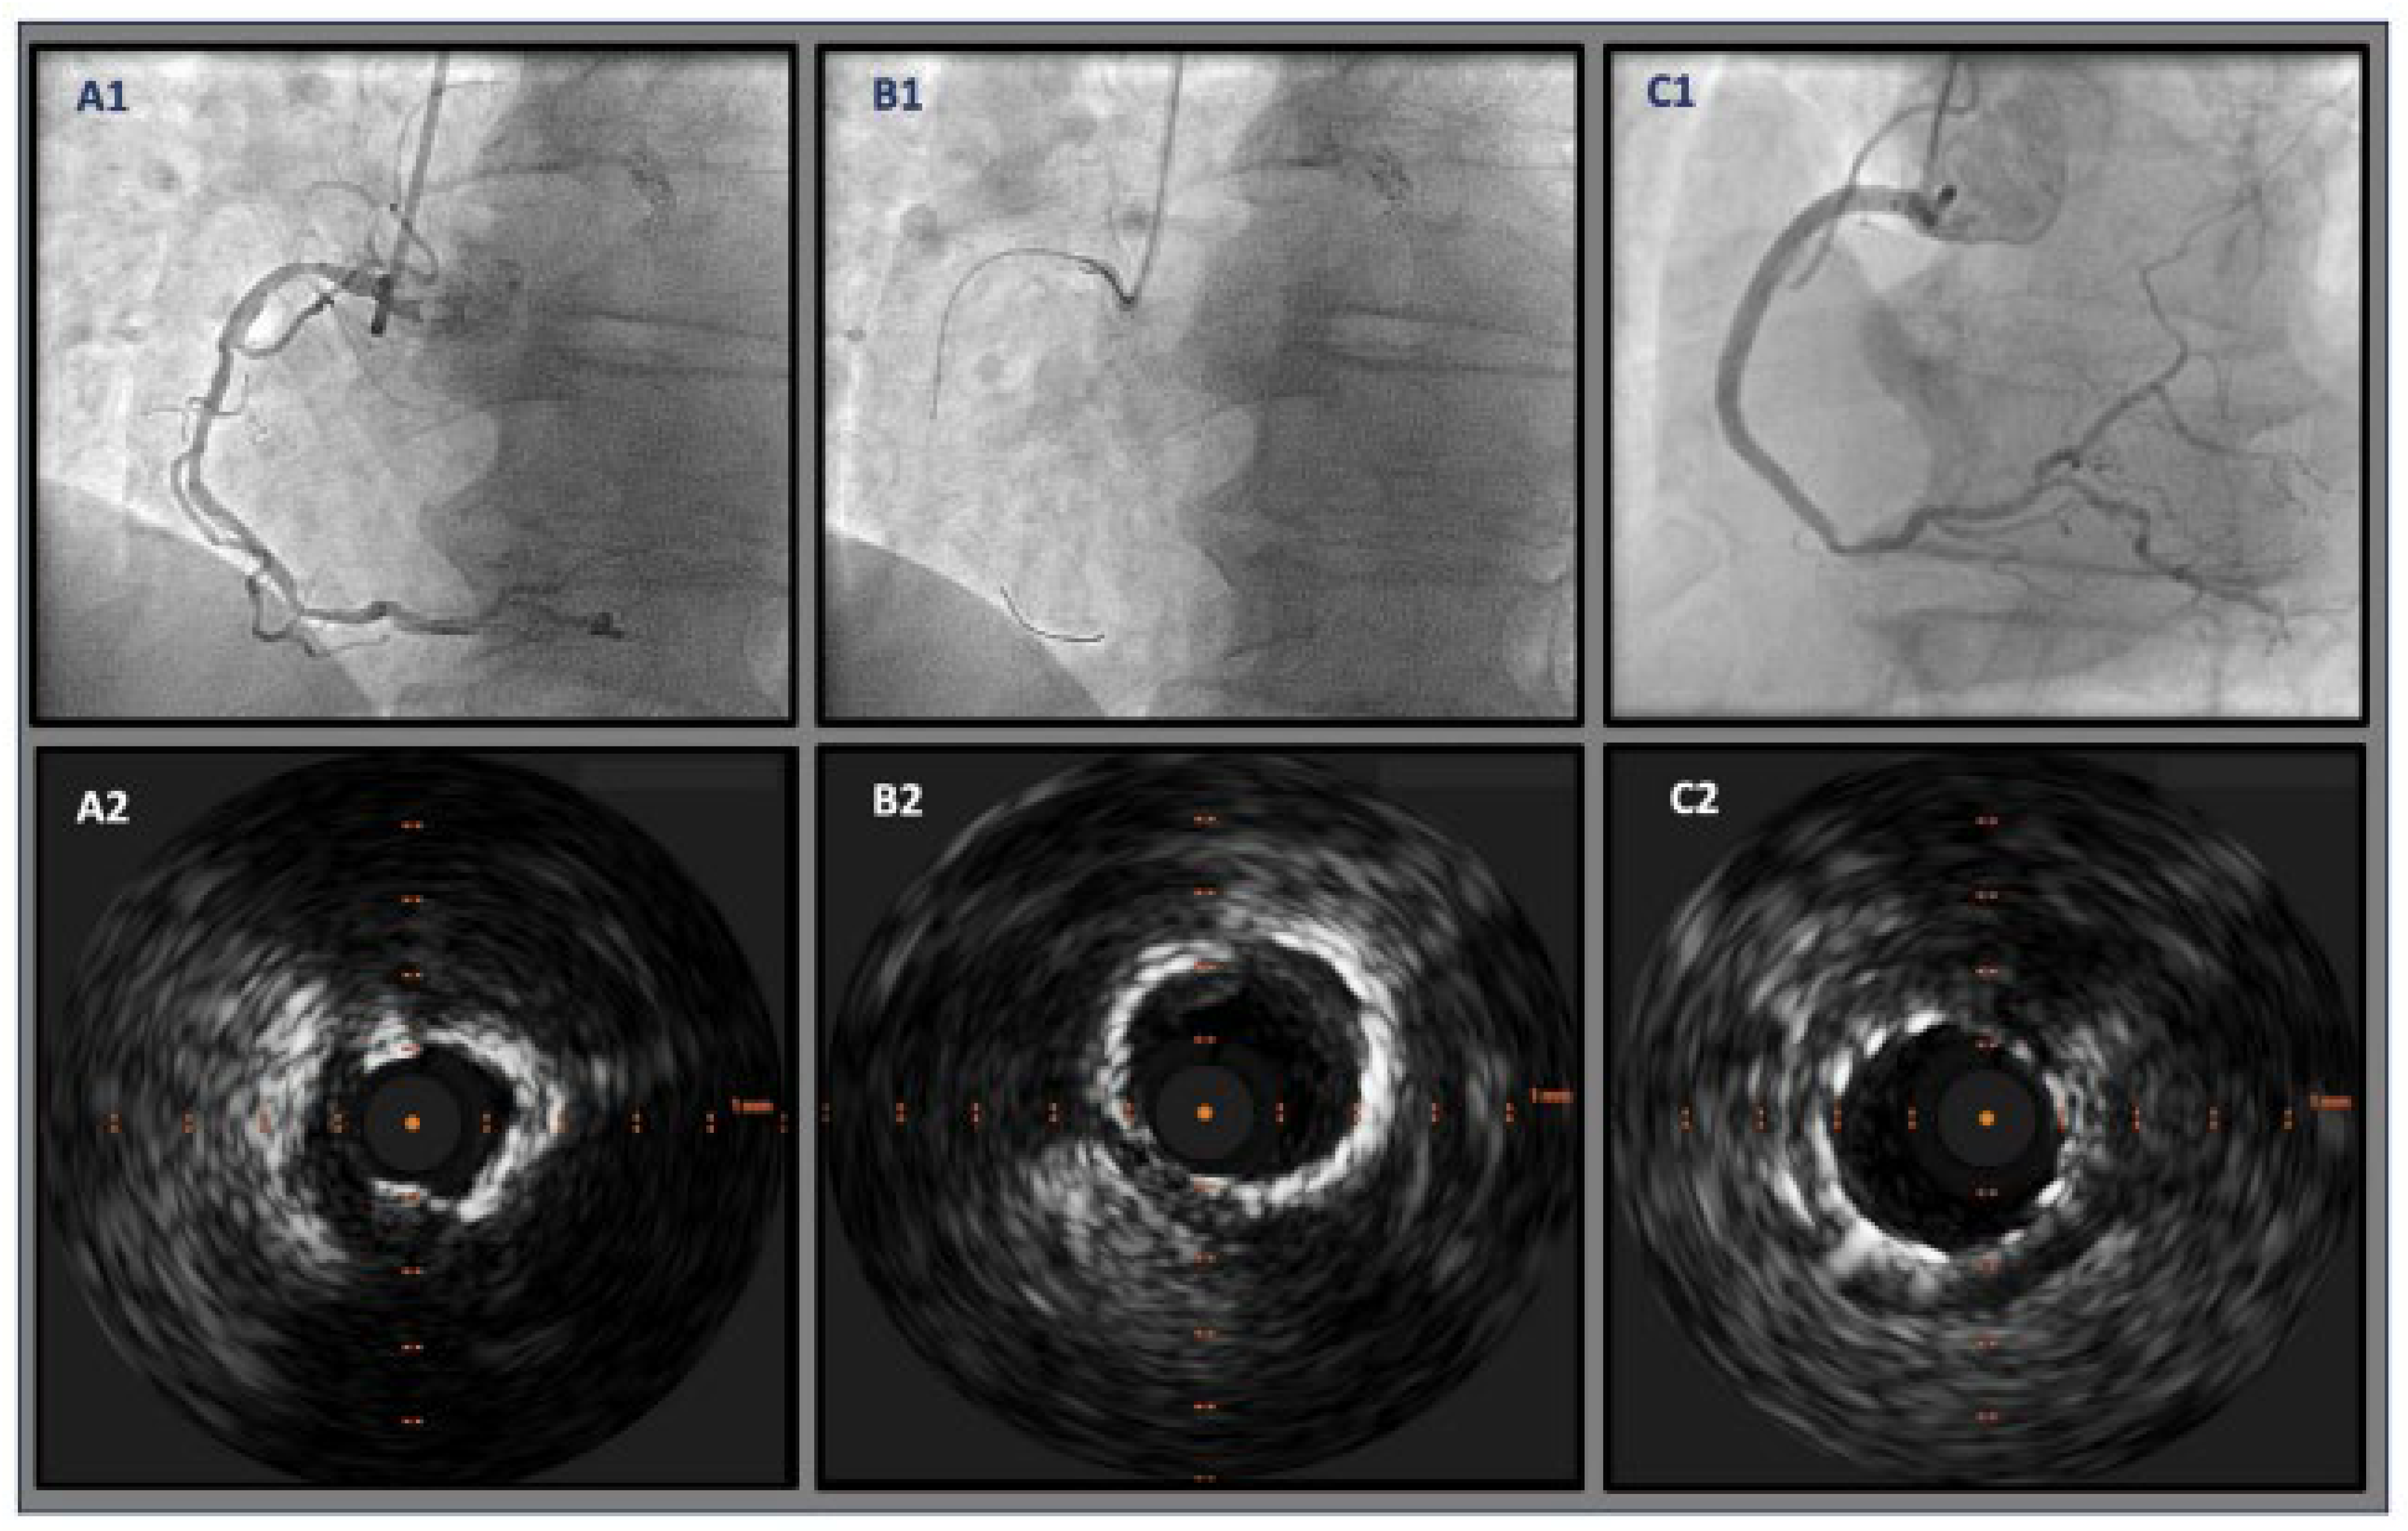

The effective execution and operation of intracoronary imaging modalities during these procedures improve both procedural and long-term clinical outcomes, particularly in intravascular ultrasound (IVUS) (Figure 6 and Figure 7) and optical coherence tomography (OCT) (Figure 8 and Figure 9), where coronary lesion morphology and mapping facilitate better PCI procedural planning [46]. Both IVUS and OCT can detect, localize, and quantify coronary calcification. Notably, OCT can visualize the calcified plaque without producing visual imaging artifacts, thereby minimizing observational scatter, and can evaluate calcium thickness more accurately than IVUS.

A 3D calcium evaluation displaying a color-coded visual depiction of calcified plaques utilizing coronary CT imagery is a remarkable feat that analyzes the calcium plaque’s location relative to the circumference of the coronary vessels while computing the location of the vessel wall in relation to the superior (epicardial) or inferior (myocardial) borders [44]. The 3D calcium evaluation through CT imagery is a tool that gauges the coronary tree’s curvature, tortuosity, and radius while assisting in predicting the path of the guide wire to prevent or minimize contact with calcium plaque deposits within the vessel.